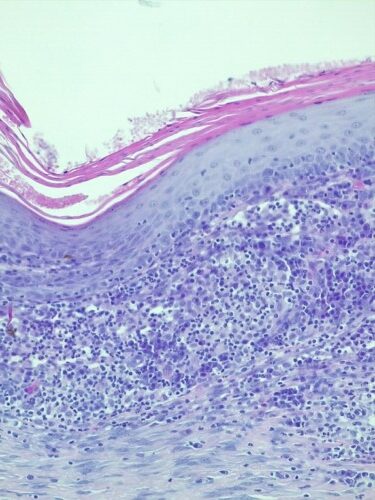

L’examen histopathologique de biopsies cutanées révèle une sévère dermatite granulomateuse lichénoïde et nodulaire périannexielle (photos 8 et 9). Les colorations PAS et fite faraco ne révèleront aucun agent pathogène.

Photo 9 : Examen histopathologique de biopsies cutanées (HES, x200) infiltrat granulomateux lichénoide